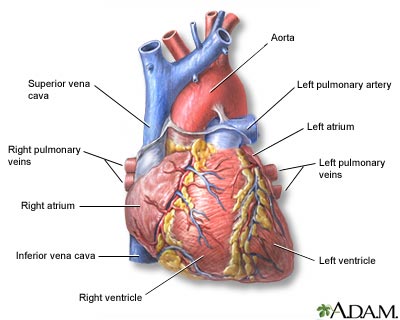

- Before birth, the baby has a blood vessel that runs between the aorta (the main artery to the body) and the pulmonary artery (the main artery to the lungs), called the ductus arteriosus. This small vessel most often closes shortly after birth when the baby starts to breathe on their own. If it does not close. It is called a patent ductus arteriosus. This could cause problems later in life.

- In a normal heart, the aorta comes from the left side of the heart, and the pulmonary artery comes from the right side. In children with transposition of the great vessels, these arteries come from the opposite sides of the heart. The child may also have other birth defects.

- The most common repair is called an arterial switch. The aorta and pulmonary artery are divided. The pulmonary artery is connected to the right ventricle, where it belongs. Then, the aorta and coronary arteries are connected to the left ventricle, where they belong.

- Truncus arteriosus is a rare condition that occurs when the aorta, coronary arteries, and pulmonary artery all come out of one common trunk from the heart. The disorder may be very simple, or very complex. In all cases, it requires open-heart surgery to repair the defect.

- A series of three heart operations is most often needed. The first operation is done in the first week of the baby's life. This is a complicated surgery where one blood vessel is created from the pulmonary artery and the aorta. This new vessel carries blood to the lungs and the rest of the body.